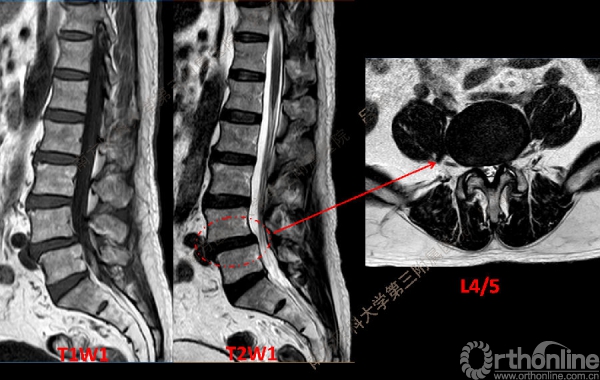

随着社会老龄化进程加快,胸腰椎退行性病变的治疗已经成为脊柱学术界的一个热点话题。MIS-TLIF手术可以治疗多种不同的胸腰椎退行性疾病,南方医科大学第三附属医院吕海教授结合病例为我们一一展示了该术式在治疗不同胸腰椎疾病时的具体手术过程。